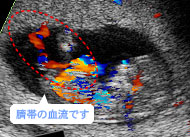

赤と青の帯が血流。母體(tǐ)(胎盤)と胎児は臍帯でつながっているんです。(妊娠12週)